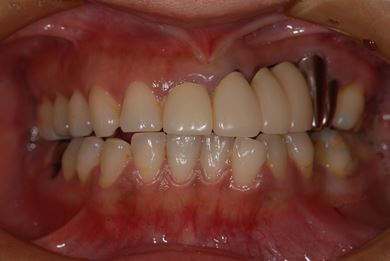

インプラントの症例写真 IMPLANT

| 主訴 | 以前治療した歯の歯ぐきから出膿。他の歯科でインプラントかブリッジしか方法がないが、骨の状態からインプラント治療は無理かもしれないと言われたことに不安を感じ、セカンドオピニオンを求めて来院。 | ||||||||||||||||||||||||||||||||

| 治療方針 | 保存不能の歯を抜歯し、インプラント治療にて機能的・審美的回復を行う。 | ||||||||||||||||||||||||||||||||

| 治療内容 | インプラント1本、ハイブリッドセラミッククラウン1本 | ||||||||||||||||||||||||||||||||